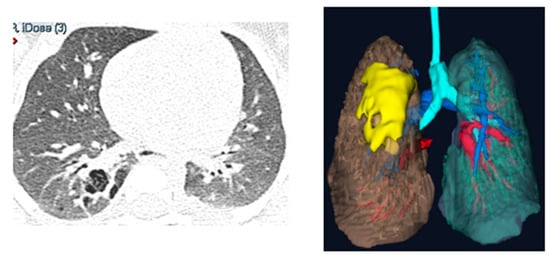

- Patient 1: affected by pulmonary cystic adenomatoid malformations, 8 months old, 10 kg weight, no other comorbidity.